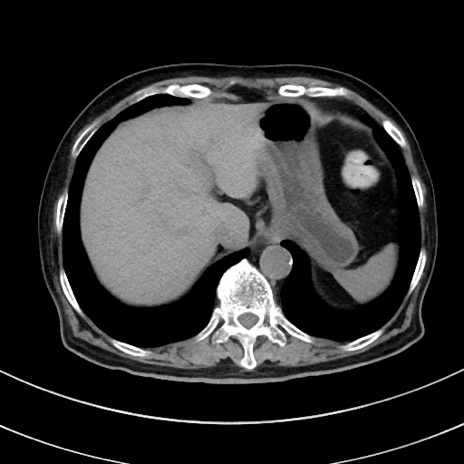

症例33(横断像)

【症例】70歳代 女性

【主訴】心窩部痛

【現病歴】延髄病変の精査・加療にて神経内科入院中。本日より心窩部痛あり。

【既往歴】虫垂炎

【身体所見】右下腹部を中心に圧痛と反跳痛あり。

【データ】WBC 10900、CRP 0.02